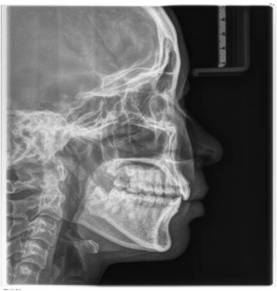

后来才知道车医生是贝恩口腔的正畸科主任,非常的专业。我先是讲了自己的牙齿的问题,车医生耐心的听完后带我去拍了牙片,从牙片上能很清晰的看出我的牙齿有点深覆合,并且牙缝也挺大的。